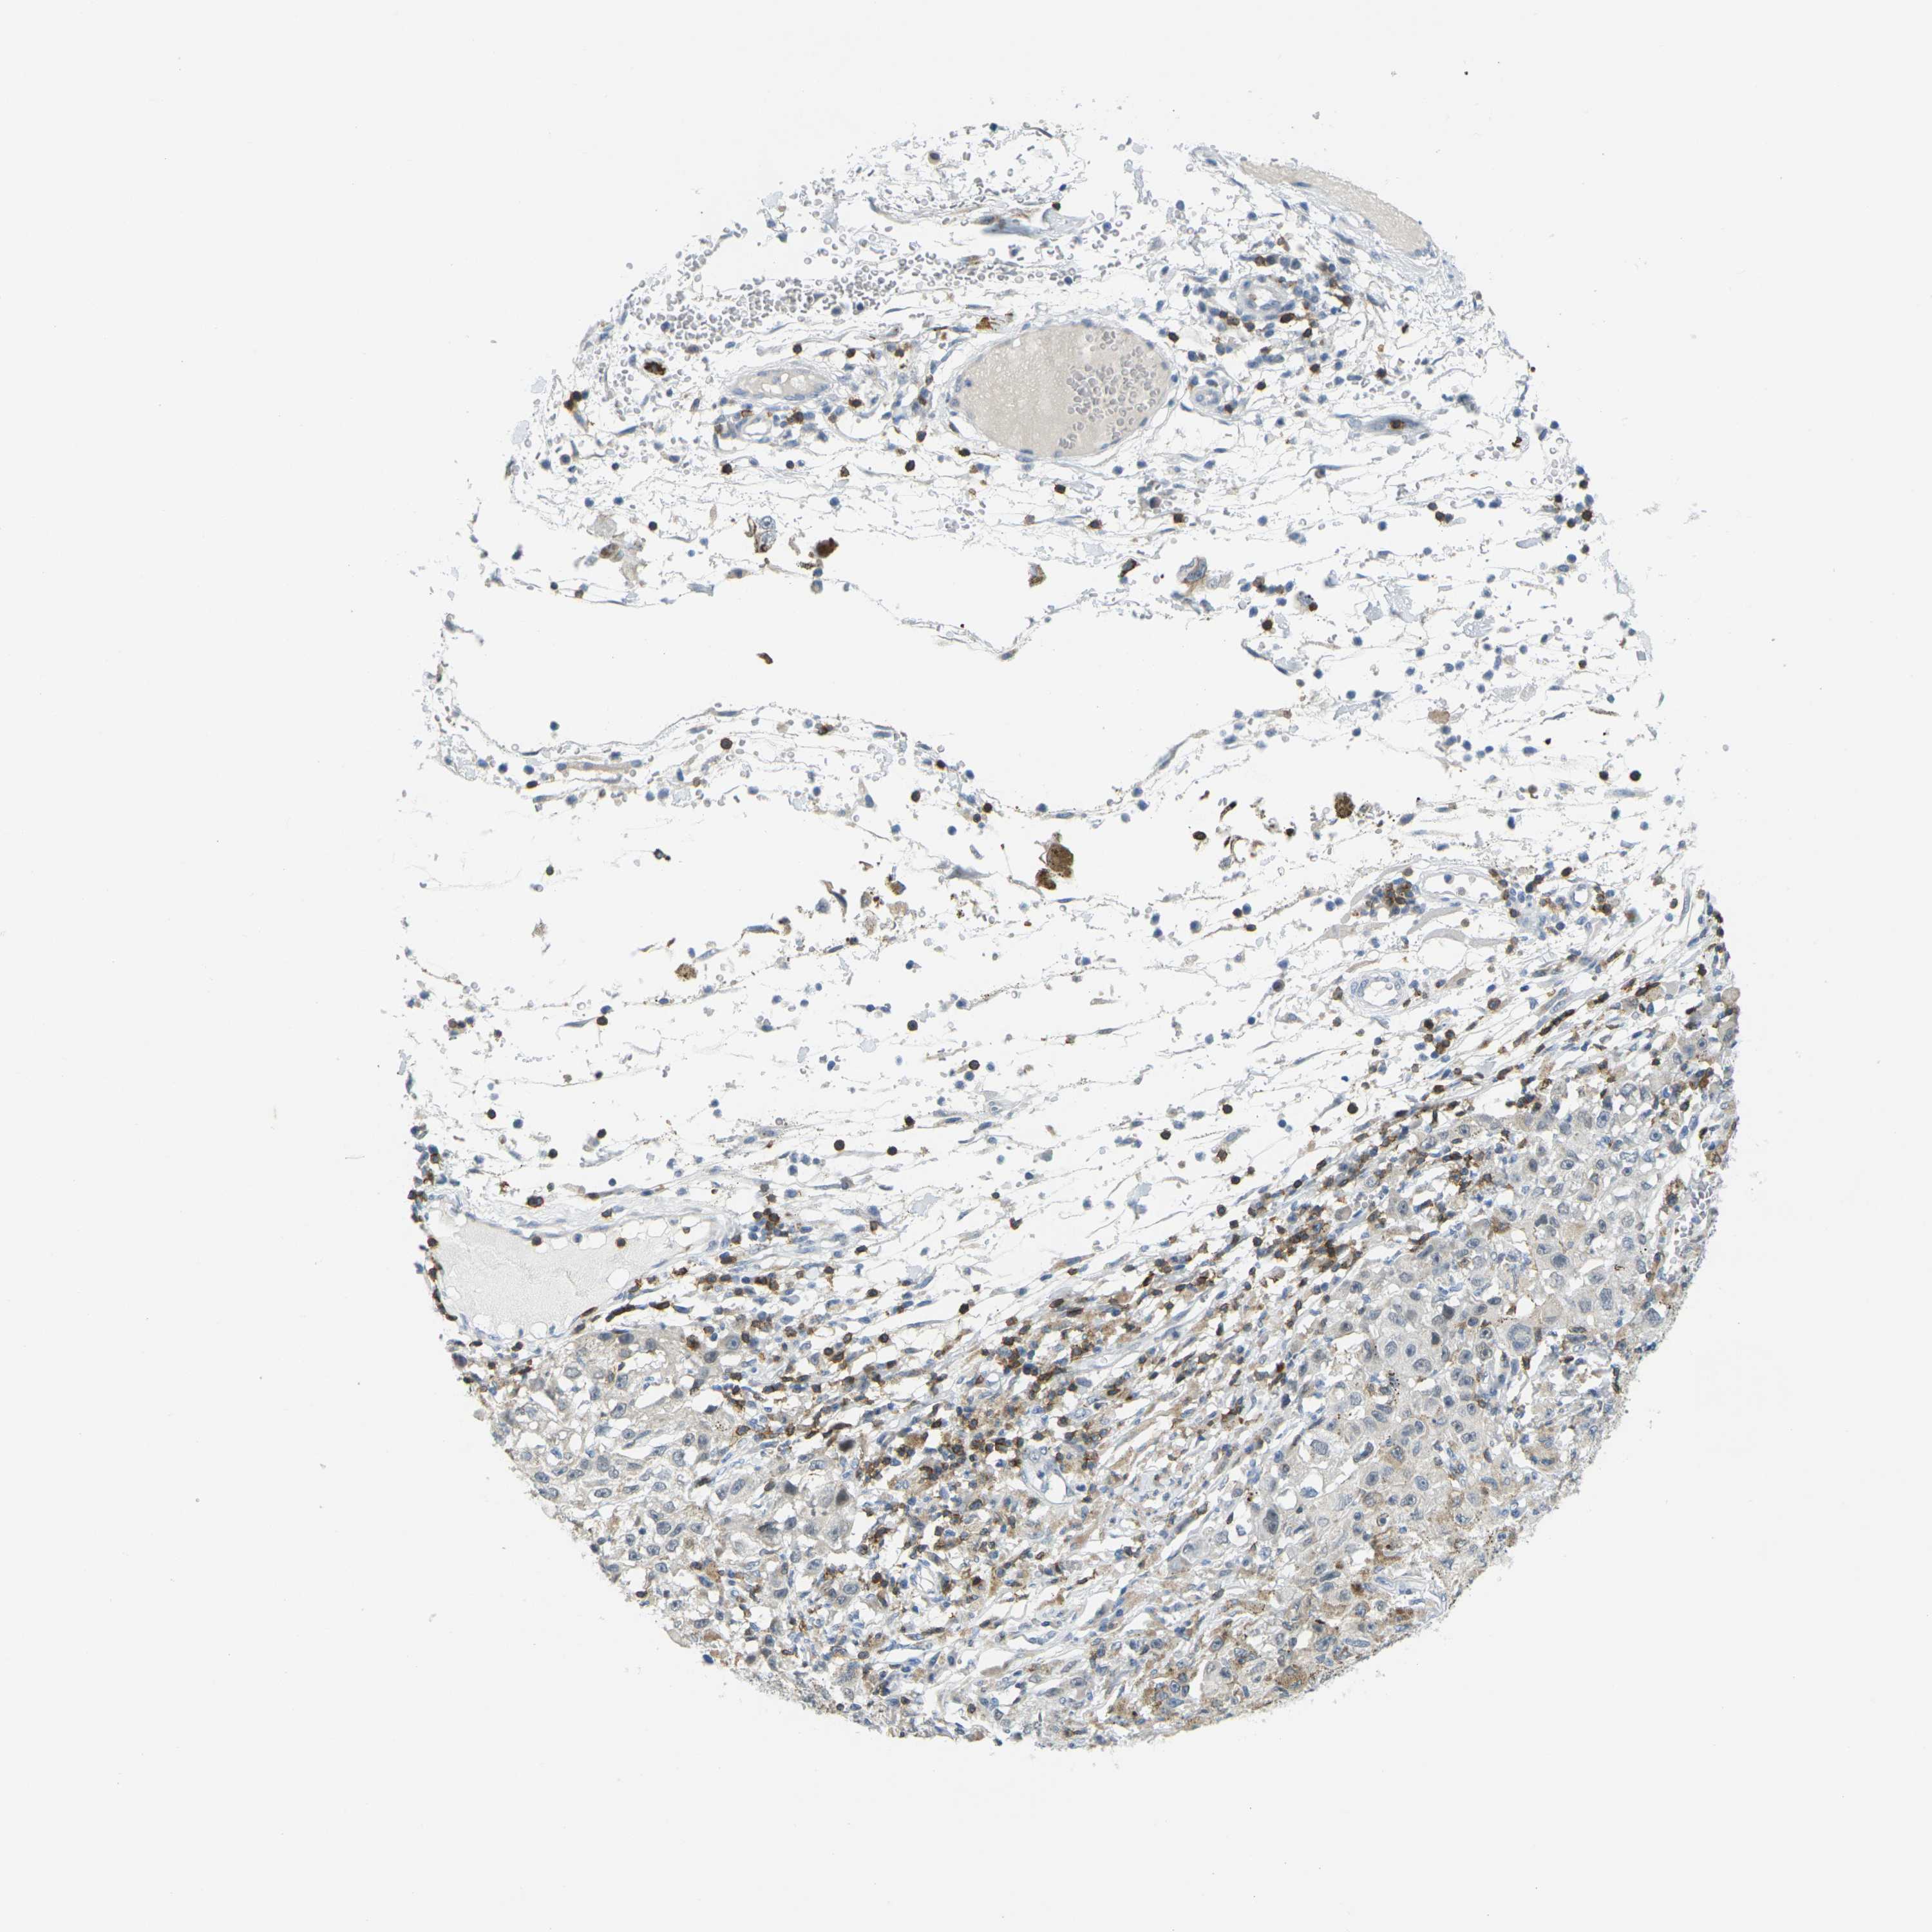

MELANOMA - Protein expressioni

A mouse-over function shows sample information and annotation data. Click on an image to view it in a full screen mode. Samples can be filtered based on level of antibody staining by selecting one or several of the following categories: high, medium, low and not detected. The assay and annotation is described here.

Note that samples used for immunohistochemistry by the Human Protein Atlas do not correspond to samples in the TCGA dataset.

Antibody stainingi

Antibody staining in the annotated cell types in the current human tissue is reported as not detected, low, medium, or high, based on conventional immunohistochemistry profiling in selected tissues. This score is based on the combination of the staining intensity and fraction of stained cells.

Each image is clickable and will lead to virtual microscopy that enables deeper exploration of all samples and also displays staining intensity scores, fraction scores and subcellular localization as well as patient and tissue information for each sample.

Antibody HPA071778

Antibody CAB013055

Malignant melanoma, NOS

Malignant melanoma, Metastatic site

Malignant melanoma in situ